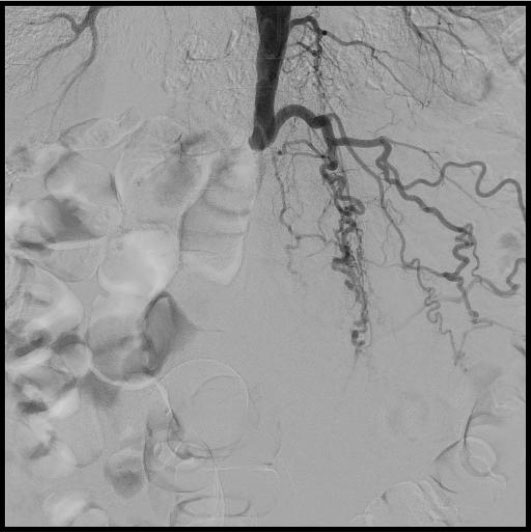

В ходе обследований было выявлено критическое поражение сосудов – ниже отхождения почечных артерий полная окклюзия (закупорка) брюшного отдела аорты, левой и правой подвздошных артерий. Кровоток к бедренным артериям и ниже доходил в недостаточном количестве, через обходные сосуды (коллатерали).

Пациенту была выполнена высокотехнологичная миниинвазивная эндоваскулярная операция – баллонная ангиопластика и стентирование брюшного отдела аорты, левой и правой подвздошных артерий, с хорошим результатом, с полным восстановлением прямого кровотока на всем протяжении обеих нижних конечностей. Данная операция миниинвазиваная, длилась 2.5 часа, была выполнена через 2 маленьких прокола в руке и ноге под местной анестезией и является альтернативой большой и долгой полостной операции, с разрезом брюшной полости под общим наркозом, которые чаще всего выполняются при таком сложном поражении.